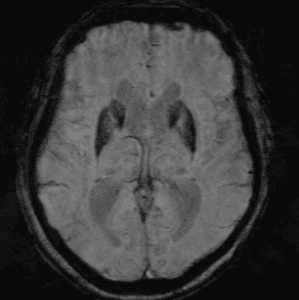

Neurodegenerative Diseases